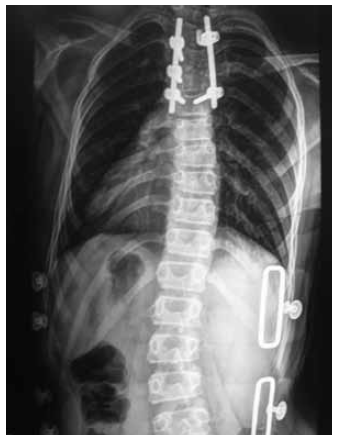

Radiographs of the spinal column revealed the existence of a hemivertebra at Th4 vertebral level with deformity angles, where the upper thoracic left-sided local scoliotic arch at the level of the hemivertebra was 30°, and the local kyphosis was 31°. Moreover, right-sided scoliotic chest arch was 36°, and the thoracolumbar scoliotic left-sided arch was 22°, according to Cobb. The size of the thoracic kyphosis was 36°, and the value of lumbar lordosis was 39°, according to

Cobb.

The radiographs of the spine of the patient upon admission to surgical treatment of congenital spinal deformity are presented in Fig. 1.

Fig. 1. Radiographs of the spine of the patient F., 11 years old, in two views before the surgical treatment